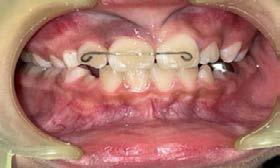

Manejo de clase II esquelética y dental mediante avance mandibular con bite ramps

Se describe un caso de un paciente masculino de 18 años de edad, con diagnóstico de clase II esquelética, normodivergente, clase II canina y molar bilateral, overjet aumentado, laterales microdónticos, apiñamiento leve superior e inferior, asimetría facial, canteamiento oclusal y con hábito de deglución atípica. Objetivos: mejorar el perfil facial, corrección del apiñamiento maxilar y mandibular, del overjet y overbite y de las líneas medias dentales, así como la obtención de clase I molar y canina bilateral. Generar remodelación condilar a largo plazo, corrección de hábito, lograr correcta intercuspidación, lograr guía de desoclusión canina, lograr guía incisiva, gingivectomía, exodoncias de terceros molares 18, 28, 38 y 48 y restauración de incisivos superiores 11, 12, 21 y 22. Tratamiento: alineación, nivelación, avance mandibular, stripping, detallado y retención. A través de brackets prescripción Roth 0.022 x 0.028”, tubos bondeables en primeros y segundos molares y bite ramps angulados en incisivos centrales superiores 11 y 21. El tiempo activo de tratamiento fue de 1 año y 4 meses, la retención se llevó a cabo mediante retenedores circunferenciales con cinturón vestibular en ambas arcadas y un Frankel unilateral izquierdo de uso nocturno.

Palabras clave: clase II, avance mandibular, bite ramps, asimetría facial, canteamiento oclusal.

En el campo odontológico se entiende por oclusión a las relaciones entre los dientes del mismo arco, de ambas arcadas, y de ellos con el resto de las estructuras y tejidos blandos bucofaciales y peridentales, en el caso del contacto entre ellos y durante todos los movimientos funcionales de la mandíbula. Proffit refiere que la maloclusión “no es más que toda aquella situación en la cual la oclusión no cumple ciertos parámetros considerados normales”. La maloclusión ósea procede de una relación anormal de la base maxilar superior e inferior.1 La maloclusión clase II esquelética y dental es multifactorial, ocasionada por factores generales y locales1 o por deficiencia en el crecimiento condilar mandibular, fracturas condilares, adaptación de la articulación temporomandibular, herencia, malformaciones genéticas, anquilosis y algunos hábitos, entre otros.2,3 La prevalencia de pacientes clase II esquelética en la población mexicana es de 37.1%4 y clase II dental división 1 en hombres mexicanos es de 11.8%.3 Se ha reportado que con avance mandibular se estimula la regeneración no solo de la fosa glenoidea sino también de la cabeza condilar.4 Como retención es importante mencionarle al paciente el uso de aparatología miofuncional para seguir promoviendo la regeneración a nivel de la articulación temporomandibular (ATM).

Caso clínico

Paciente masculino de 18 años de edad con motivo de consulta: “Quiero arreglar toda mi dentadura”, diagnosticado con clase II esquelética, biotipo facial mesofacial, perfil convexo, clase II canina y molar bilateral, línea media superior coincidente con la facial, línea media inferior desviada a la izquierda 2 mm, overjet aumentadado con 9 mm y overbite disminuido a 17%.

Estudios extraorales y fotografías de inicio

En la Figura 1 se observa el biotipo mesofacial del paciente con quintos proporcionales. En la Figura 2 el tercio medio aumentado respecto al tercio inferior y superior. La Figura 3 la sonrisa la línea media facial coincidente con la dental superior y ligera asimetría facial hacia la izquierda.

Estudios intraorales de inicio

En la fotografía lateral derecha (Figura 4), de frente e izquierda se ve la clase II canina y molar bilateral, curva de Spee acentuada y laterales microdónticos. La línea media dental inferior está desviada a la izquierda 2 mm. En las oclusales superior e inferior, el apiñamiento leve superior e infierior, laterales superiores

Figura 1. Frente.

Figura 2. Perfil.

Figura 3. Sonrisa.

microdónticos y formas de arco cuadradas (Figura 5).

Estudios iniciales radiográficos de inicio

En la radiografía lateral de cráneo ( Figura 6 ) se ve la línea estética de Rickets, que el labio superior se encuentra a +0.5 mm y el inferior a -2 mm. En las mediciones cefalométricas más importantes en la figura 11 un ANB de 5º, GoGn-SN de 33º y FMA de 21º crecimiento normodivergente y Witts de -1 mm. A los criterios dentales encontramos

1-PLT de 129º e IMPA 99º proinclinación de incisivos tanto superiores como inferiores. En la radiografía panorámica (Figura 7), la presencia de 32 órganos dentarios, con terceros molares inferiores aún sin erupcionar y terceros molares superiores

Manejo de clase II esquelética y dental

Figura 4. Intraoral derecha, frente, izquierda.

Figura 5. Oclusal superior e inferior.

Figura 6. Rx. cráneo lateral inicio progreso con trazos.

7. Radiografía panorámica.

Figura 8. Cortes sagital, inclinaciones dentales superior e inferior, axial tomográfico de las arcadas.

Figura

de clase II esquelética y dental

ya erupcionados, falta de paralelismo radicular, asimetría condilar, articulación temporomandibular (ATM) izquierda afectada.

Estudios tomográficos

En el corte sagital ( Figura 8 ) se muestran las inclinaciones dentales alteradas hacia vestibular de ambos incisivos. Finalmente en una vista

axial la forma de arcos cuadrada y la malposición dental clasificada como apiñamiento leve.

Tratamiento

El tratamiento consistio en alineación, nivelación, avance mandibular, stripping, detallado y retención. La corrección del apiñamiento maxilar y mandibular se resolvió a través de

9. Bondeo indirecto con silicona.

a) Marcaje de línea media asentada.

b) Retiro de guía de silicona

Figura 10. Intraorales de bondeo superior realizado por técnica indirecta.

Figura 11. Uso de elásticos clase II bilaterales dobles y “Storino Leash” en sector anteroinferior.

12. Intraorales uso de elásticos en W y bite ramps largos en sector anterosuperior.

13. Extraorales de sonrisa.

Julio 2024

Manejo

alineación y nivelación haciendo uso de la técnica de bondeado indirecto (Figura 9 y 16) con secuencia de arcos CuNiTi 0.016” superior, NiTi 0.016, 0.016” x 0.022”, 0.017” x 0. 025” y acero inoxidable 0.018”.

La obtención de clase I canina y molar bilateral se obtuvo mediante el avance mandibular y uso de elásticos intermaxilares con el uso de bite ramps en 11 y 21 angulados largos, elásticos clase II cortos y largos de 3/16” 4.5 oz sencillos y dobles figura 10 y elásticos clase II continuos en W de uso nocturno de 5/16” 2.5 oz (Figura 1). La corrección del overjet y overbite se alcanzó con anclaje mínimo, elásticos intramaxilares, IPR, rebondeo y arcos seccionales mediante ferulizado con ligadura metálica de segundo molar superior derecho 17 a canino superior derecho 13 y de lado contrario de 27 a 23, tie back inferior, stripping de 33 a 43, cadena de canino a canino superior de 13 a 23 y de primer molar a primer molar inferior de 36 a 46, “Storino Leash" anteroinferior de 33 a 43, rebondeo con alturas Pitts en anterosuperior y arcos seccionales de NiTi 0.016”. Máxima intercuspidación, paralelismo radicular y

oclusión funcional tratatada bajo el detallado del caso con arcos de acero inoxidable 0.017” x 0.025”, 0.019” x 0.025”. Dobleces de segundo orden: Tip mesial de caninos superiores 13 y 23, intrusión de segundos premolares superiores 15 y 25 y de anteroinferiores de 32 a 42, extrusión de primeros premolares 14 y 44 incisivios 22, 42 y 21 al igual que segundos premolares inferiores 35 y 45, por último en el detallada se ocuparon elásticos en W para asentamiento.

Resultados

Se logró una sonrisa más armoniosa respetando la línea media facial de inicio a final (Figura 13). En la Figura 14 la mejoría en el perfil, con mejor protracción del mentón debido al avance mandibular y como el tercio medio permaneció aumentado de inicio a fin.

Secuencia de radiografías laterales de cráneo (Figura 15) vemos que el ANB disminuyo 1º de inicio a fin clase I con tendencia a clase II esquelética a final. Reducción de Witts 0.5 mm final, crecimiento normodivergente. Mandíbula más pequeña que el maxilar, cambio por el avance mandibular.

Figura 14. Extraorales de perfil.

Figura 15. a) Rx lateral de cráneo de inicio. b) De progreso. c) Lateral de cráneo final.

Referente a los criteriso dentales, el incisivo maxilar respecto a su base ósea tuvo una importante retroinclinación, inció en 129º y finalizó en 111º, en cuanto al incisivo inferior, este se proinclinó 1º, de 99º a 100º.

Panorámicas de inicio a fin (Figura 16) el paralelismo radicular, genera estabilidad a largo plazo en el tratamiento. Se extrajeron los terceros molares para eliminar discrepancia posterior y lograr adecuada

Figura 16. Radiografías panorámicas. a) Inicio. b) Progreso. c) Final.

distalización. Se alineo la curva de Spee acetuada y se libero correctamente el apiñamiento dental que presentaba el paciente al inicio del tratamiento.

En los estudios intarorales finales (Figura 17), se observa la coincidencia de las líneas medias, la resolución del apiñamiento leve, adecuado overjet y overbite y restauración de los laterales microdónticos.

La estabilidad a largo plazo con retenedor removible superior e inferior circunferencial en ambas arcadas (Figura 22) de uso nocturno de Frankel (Figura 16), unilateral

izquierdo para promover la regeneración condilar del lado afectado.

Sobreimposiciones incio-final sobre componente craneofacial figura 20 paciente adulto sin crecimiento, con descenso y avance mandibular con bite ramps, modificación en el perfil facial a nivel de labio inferior y proyección del mentón. Sobre maxilar (Figura 21) extrusión y ligera distalización del primer molar superior y retroinclinación y ligera extrusión del incisivo superior pasa de 1-PLT de 129º a 111º. Sobre sínfisis figura 22 ligera extrusión y verticalización del molar inferior y proinclinación y extrusión del incisivo inferior,

Figura 17. Fotografías intraorales de frente. a) Inicio. b) Progreso. c) Final.

Figura 18. Vista oclusal y frente de los retenedores circunferenciales.

determinada por el uso de la mecánica de adelantamiento mandibular.